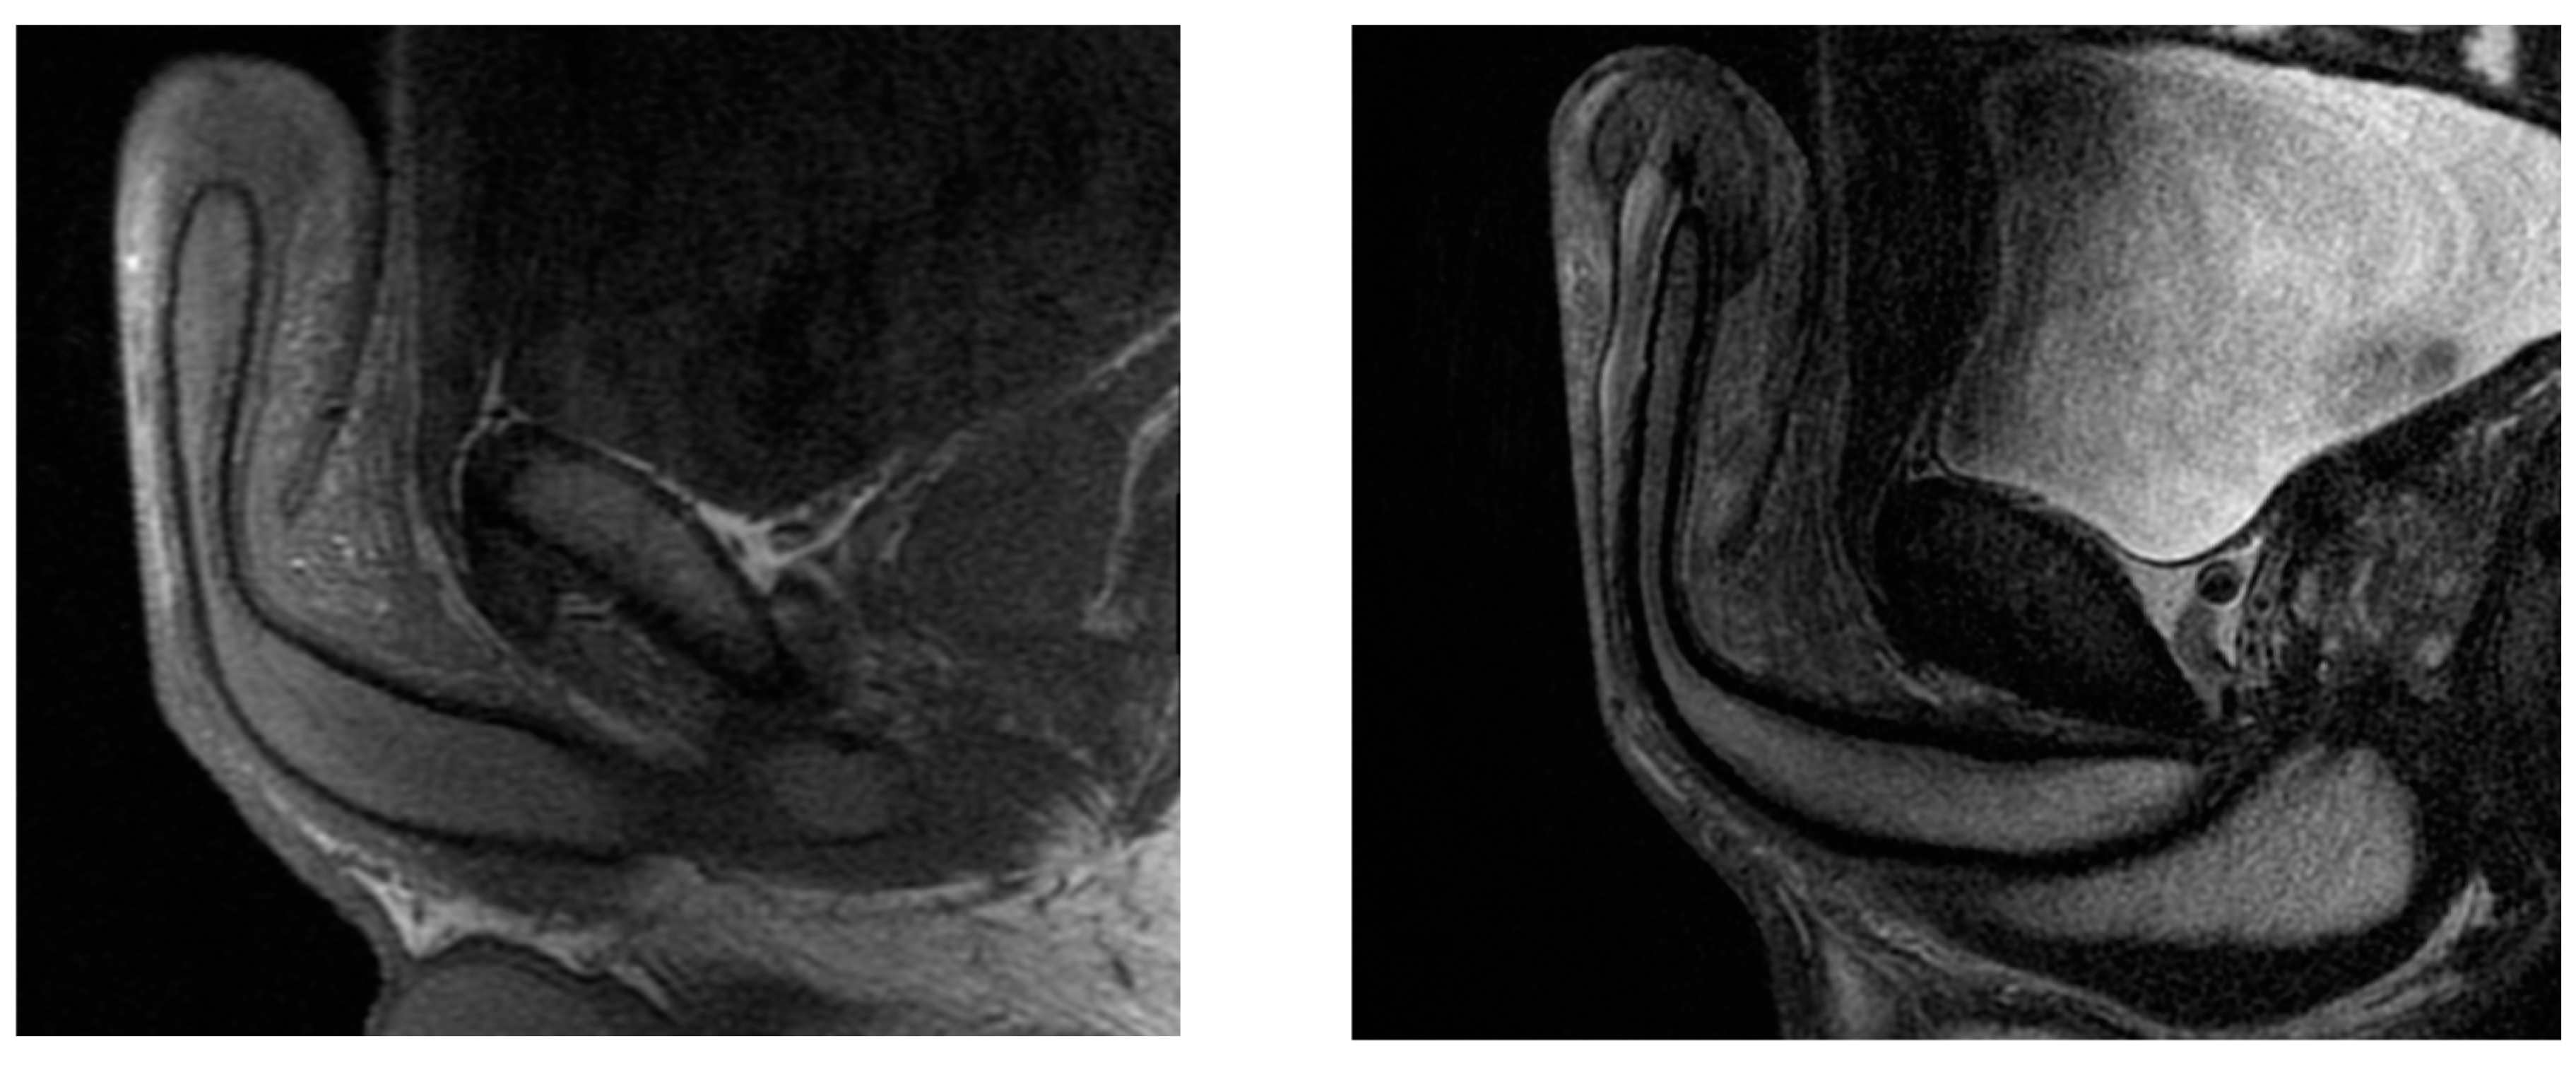

- Cormio, L.; Di Fino, G.; Scavone, C.; Selvaggio, O.; Massenio, P.; Sanguedolce, F.; Macarini, L.; Carrieri, G. Magnetic resonance imaging of penile paraffinoma: Case report. BMC Med. Imaging 2014, 14, 39. [Google Scholar] [CrossRef] [PubMed]